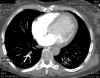

Video 2 - Echokardiograficky byla zjištěna těžká dysfunkce dilatační levé komory s nezvětšenou pravou komorou.Pro nejasnou příčinu zástavy jsme provedli i vyšetření výpočetní tomografií (CT), které vyloučilo plicní embolizaci (série 1 - soubory na konci článku). V den přijetí při přetrvávající oběhové nestabilitě byla nemocná opakovaně defibrilována pro fibrilaci komor se stabilizací rytmu po podání amiodaronu a mesocainu. Dle hemodynamických měření se jednalo o těžký kombinovaný šok. Vstupní laboratorní vyšetření bylo bez větších pozoruhodností. Posléze jsme doplnili anamnézu od příbuzných a zjistili, že pacientka užila do dvou hodin před srdeční zástavou první tabletu amoxicilinu na lehký respirační infekt. Při nevýtěžnosti vstupních vyšetření a nových anamnestických informacích jsme doplnili 14 hodin po kolapsu vyšetření koncentrace tryptázy v séru, která byla extrémně zvýšena (tabulka 2), což nás vedlo k podezření na anafylaxi.